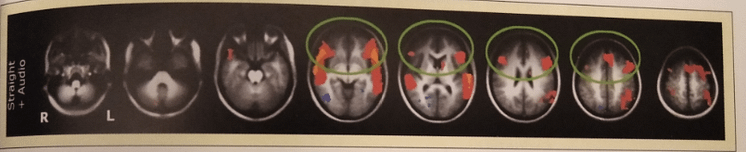

Ce m-a frapat continuand sa citesc despre atentia distributiva este ca de fapt a face 2 lucruri in acelasi timp nu cere la fel de mult efort ca suma eforturilor in executarea celor 2 activitati separat. In imaginea de mai jos, captata cu ajutorul RMN, se vede acest lucru. In 2001, Just et al. au condus un studiu in care era analizata activitatea cerebrala in  timp ce subiectii  ascultau si intelegeau un text, in timp ce roteau niste imagini 3D. S-a inregistrat activitatea cerebrala in fiecare din taskurile mentionate efectuate singular, dar si impreuna.

Surpriza experimentului a fost aceea ca activitatea zonelor responsabile pentru procesarea lingvistica a scazut cu 53% si cea responsabila de vederea in spatiu si miscarea obiectelor cu 29%.